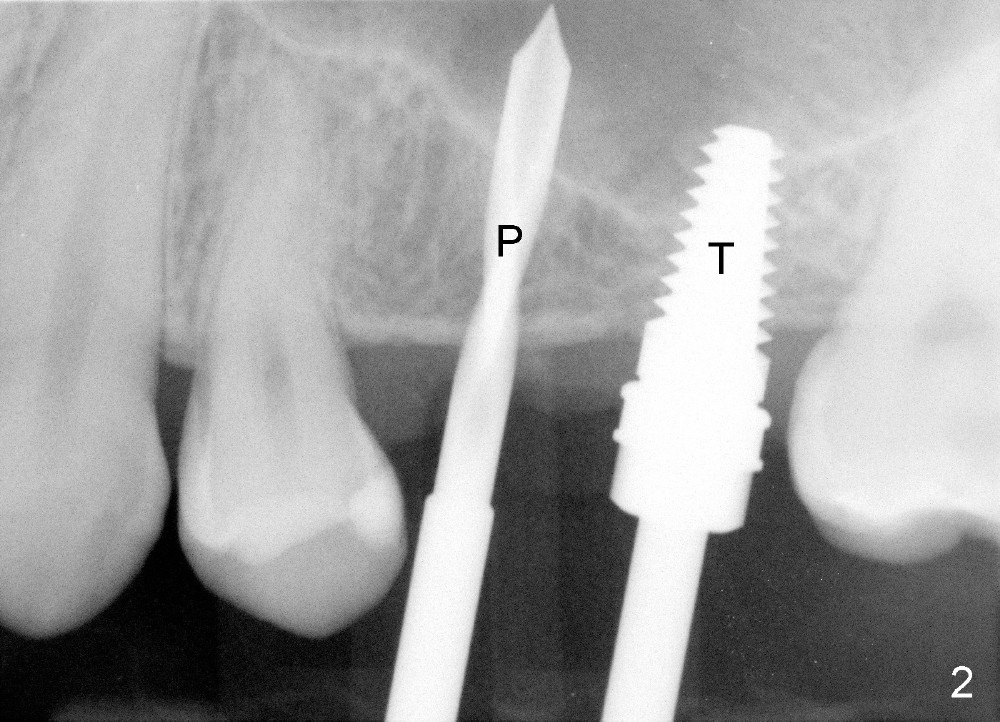

The patient returns for #13,14 implant placement. The ridge appears to be wide buccolingually (Fig.1 mirror view). A 4 mm tissue punch is used for access at the sites of #13 and 14. Osteotomy is initiated by using 3 mm trephine bur at the depth of 4 mm at both sites; 2 mm pilot drill is used to continue osteotomy at 8 mm deep at the site of #13. Sinus lift is accomplished by using tapered osteotomes 2,3 mm 6 mm deep, followed by 4.5x11 mm tap (Fig.2 T); 2 mm pilot drill (P) is reinserted into #13 osteotomy site with inadvertently penetrating the sinus floor. When the tap is removed from the site of #14, the sinus membrane is also found to be perforated. The sinus membrane at both sites is repaired by insertion of collagen dressing before bone graft. A 4x11 mm one-piece implant is placed at the site of #13 slowly hoping that it does not re-perforate the sinus membrane (Fig.3 O). Due to limited restorative height, the abutment portion of the one-piece is expected to be trimmed (Fig.4 O). In case of implant complication or failure, the implant may be difficult to be removed. Therefore the implant at the site of #14 is two piece one (Fig.4,5 I/A, 5x11 and 4x3 mm, respectively). The insertion torques for #13 and 14 are 35/40 and >60 Ncm. Immediate provisionals are canceled mainly because of patient's inability to open wide for long. Perio dressing is placed instead after adjustment of the height of the abutments. The patient experiences one episode of light nasal hemorrhage a few hours postop. Although the patient takes Amoxicillin for 1 week periop, the implant at the site of #13 dislodges 1 months postop (Fig.5). Immediate re-placement with a larger 2 piece one is canceled because of mild infection mesiobuccal to the implant at the site of #14 (Fig.6 >). Exploration around the latter implant reveals possible thread exposure in a small area. After copious irrigation with normal saline, Arestin is placed. Two months post exfoliation, the site is re-entered (Fig.7,8). There is a lingual defect. Osteotomy is initiated as buccal as possible. A 4.5x11 mm tapered tap penetrates the sinus floor without tearing the membrane (Fig.9). The same-sized implant is placed (25/30 Ncm) with sinus lift (Fig.10 *). The lingual defect is bone grafted. There is dehiscence lingually 7 days postop (Fig.11). Impression for final restoration is taken 1.5 months postop because of pending wedding. The crown has been in function for 2.5 months.